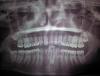

diesel87 Опубликовано 23 ноября, 2012 Поделиться Опубликовано 23 ноября, 2012 ...21:00 заканчиваю рабочую смену, крайний пациент остался, ну думаю сейчас быстренько приму и домой...пятница)))а там оказывается удаление, ну ладно думаю, быстренько уберем и все))), а удаление верхней восьмерки, так верхней думаю, тем более ерунда, а так она у меня в кости.... Ну кто в пятницу вечером приходит на удаление ретенированных восьмерок...Итог: минут 30 повозился, зато уехал домой с переизбытком чувства выполненного долга))) 1 Ссылка на комментарий

diesel87 Опубликовано 24 ноября, 2012 Автор Поделиться Опубликовано 24 ноября, 2012 Да, 28 неделю назад в другой клинике удалили, не понравилось пацу, к нам пришел дальше продолжать) Ссылка на комментарий